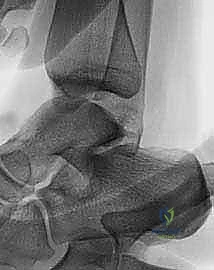

* الأشعة السينية (X-rays) مع الإجهاد: لاستبعاد الكسور وتقييم زوايا عدم الاستقرار.

* الرنين المغناطيسي (MRI): وهو الفحص الذهبي لرؤية الأنسجة الرخوة، وتحديد حجم التمزق في الأربطة، والتأكد من عدم وجود إصابات غضروفية مرافقة (Osteochondral defects).